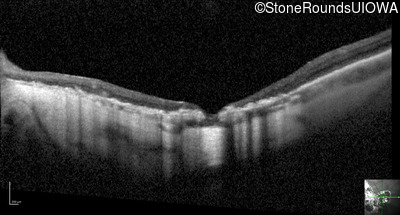

Optical Coherence Tomography - Right - 20/160 -2

Exemplar / OCT Stack